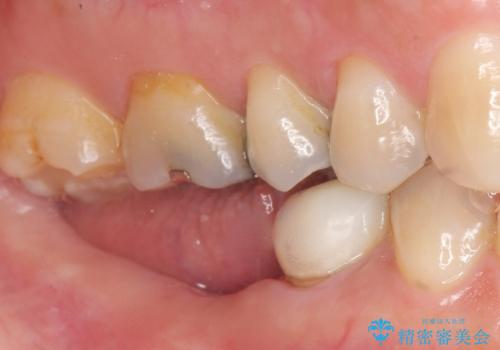

患者様のご希望により、右下大臼歯2本(右下76)のインプラント治療、右下小臼歯(右下5)の根管治療及び補綴治療を行いました。

奥歯でしっかり噛むことができるようになり、喜んで頂けました。

セラミッククラウンの審美的な仕上がりにもご満足頂けました。

クラウンの種類:ベレッツァクラウン(右下76)、ジルコニアクラウン スタンダード(右下5)